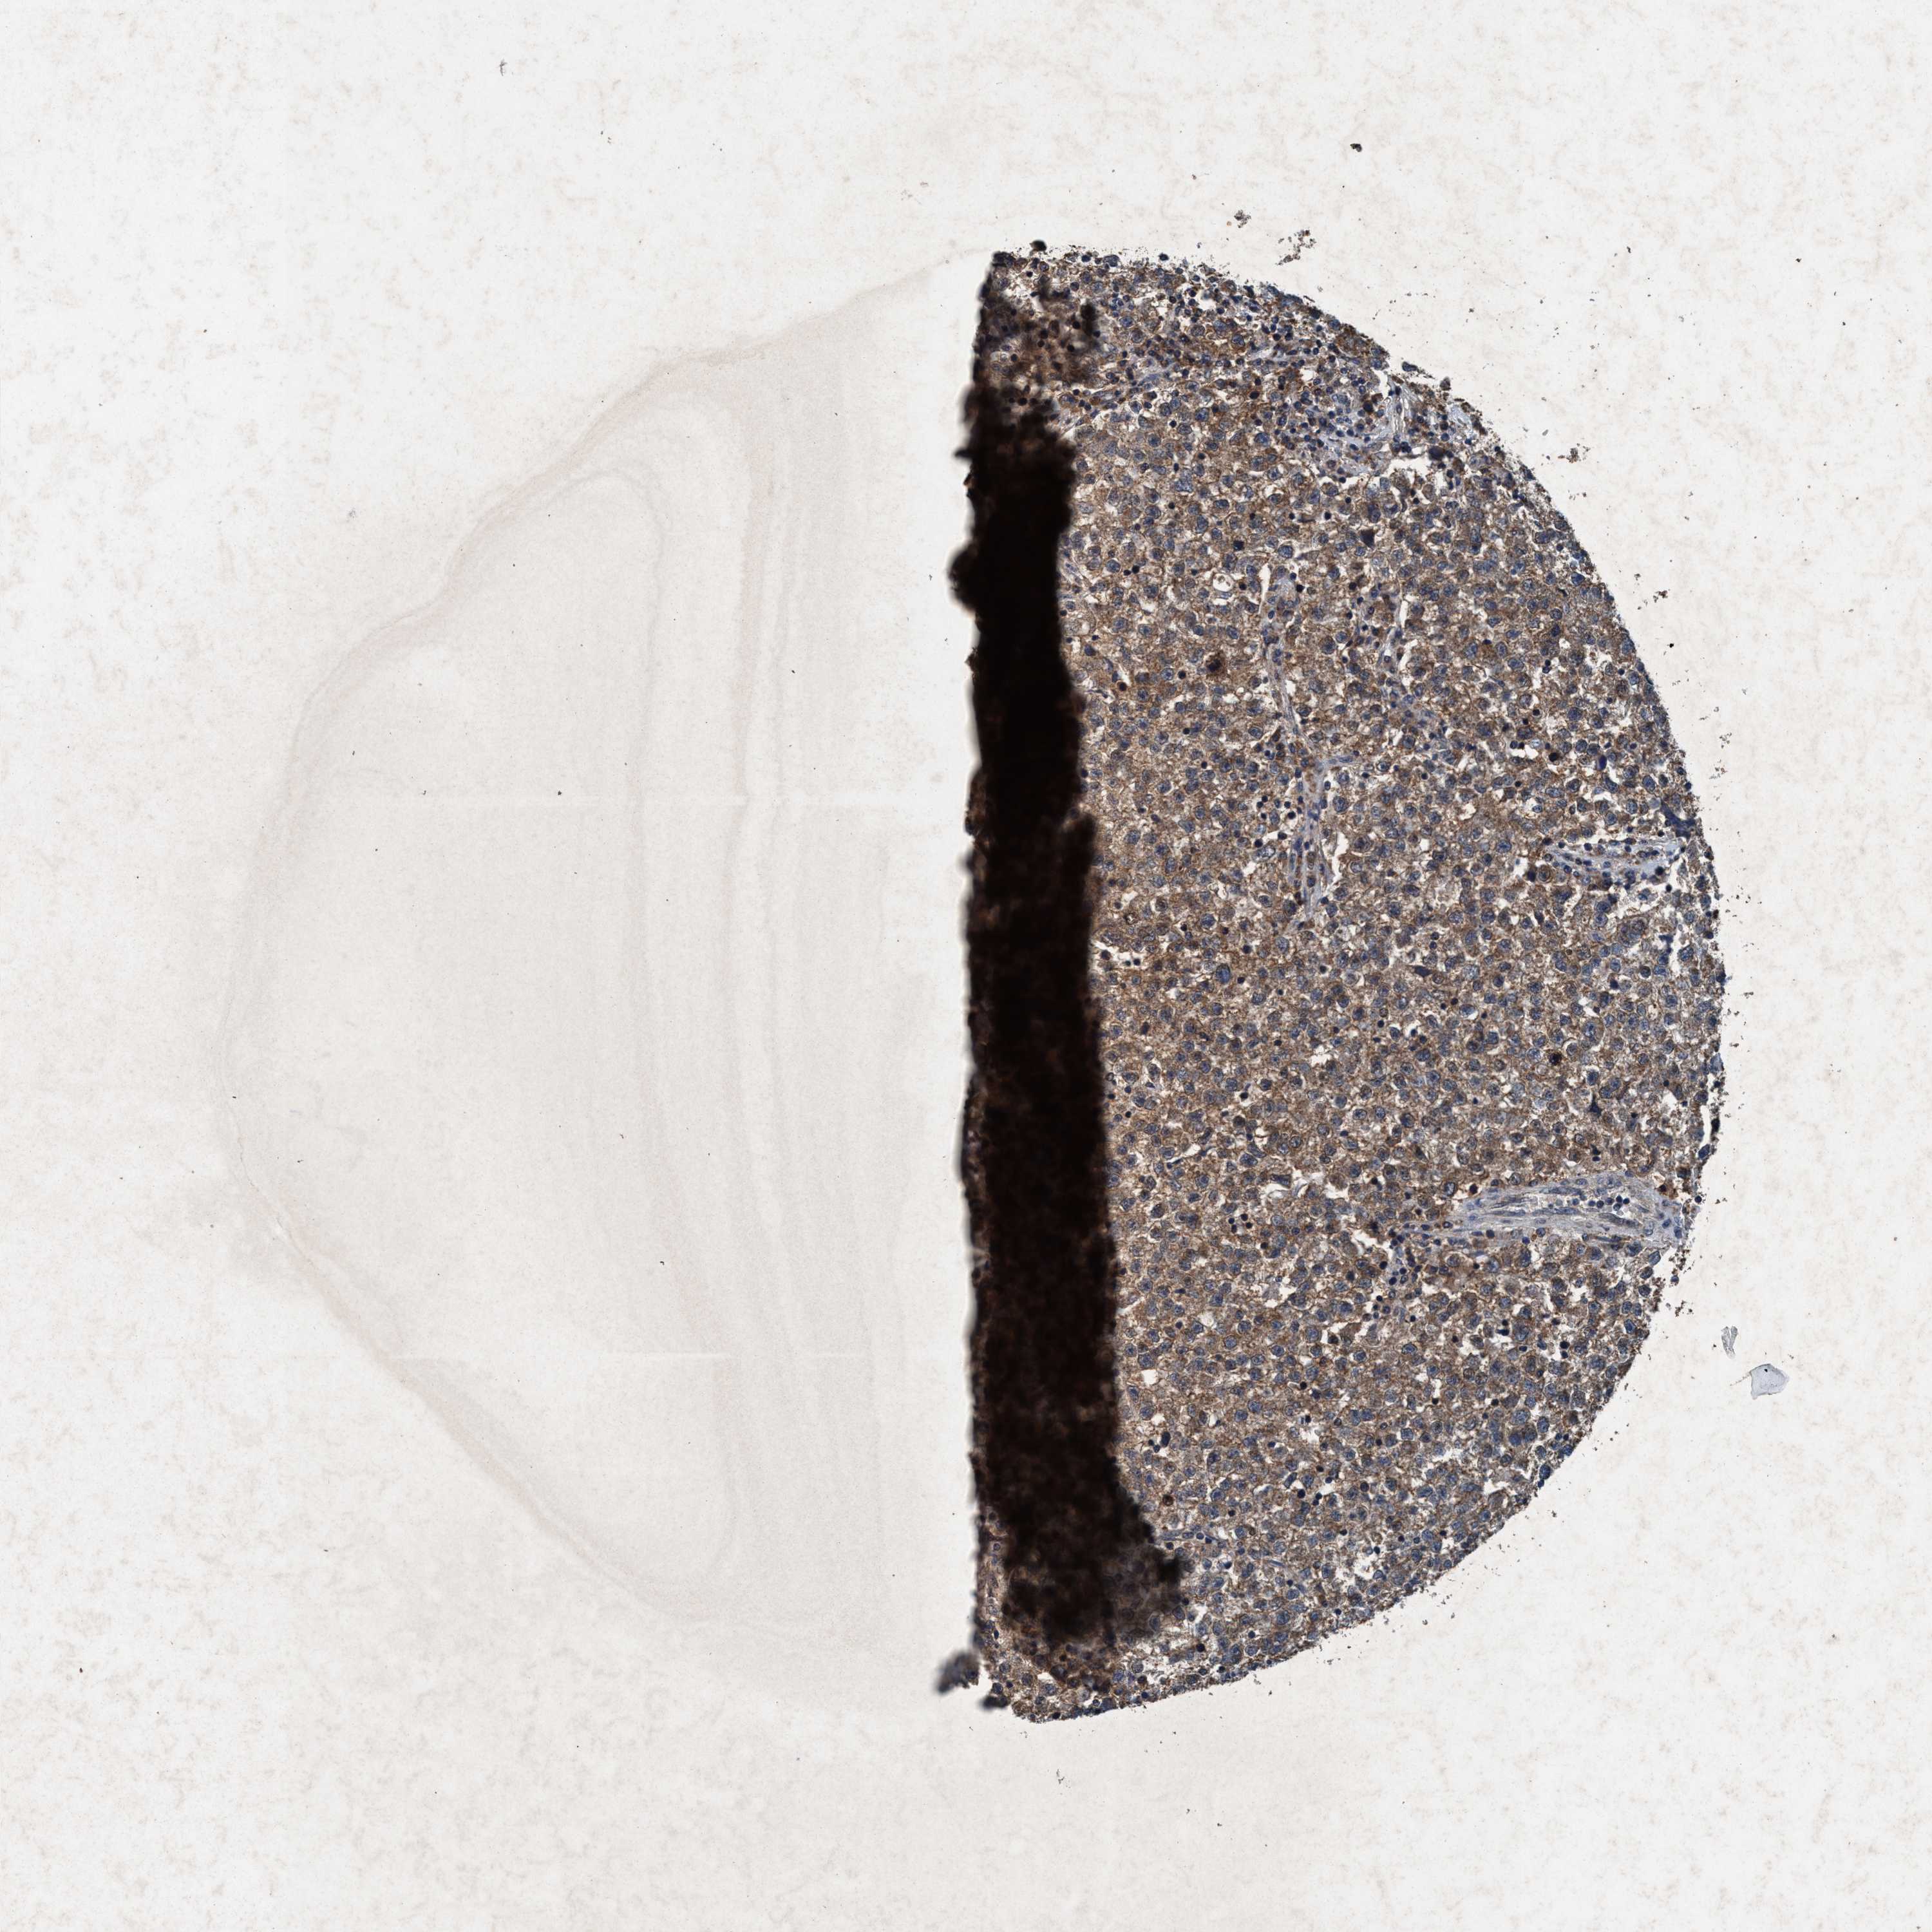

TESTIS CANCER - Protein expressioni

A mouse-over function shows sample information and annotation data. Click on an image to view it in a full screen mode. Samples can be filtered based on level of antibody staining by selecting one or several of the following categories: high, medium, low and not detected. The assay and annotation is described here.

Note that samples used for immunohistochemistry by the Human Protein Atlas do not correspond to samples in the TCGA dataset.

Antibody stainingi

Antibody staining in the annotated cell types in the current human tissue is reported as not detected, low, medium, or high, based on conventional immunohistochemistry profiling in selected tissues. This score is based on the combination of the staining intensity and fraction of stained cells.

Each image is clickable and will lead to virtual microscopy that enables deeper exploration of all samples and also displays staining intensity scores, fraction scores and subcellular localization as well as patient and tissue information for each sample.

Antibody HPA064427

Antibody HPA075510

Antibody CAB021903

Teratoma, malignant, NOS

Carcinoma, Embryonal, NOS